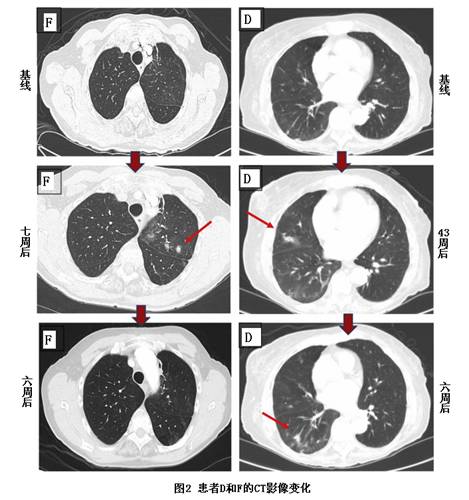

一共有7例患者(包括2例一线治疗患者)在奥希替尼治疗过程中新增无症状的局限性肺密度影,之后消失,4例重复发生。有2例被认为是吸入式肺炎,接受了抗生素治疗。TAPOs中位发生时间8.7周(范围1.6-43周),中位消失时间6周(范围1-11周),见图1。

该7例患者,5例只有单个TAPOs,2例有2个TAPOs,一共9个TAPOs,6个在肺下叶,1个在肺中叶,2个在肺上叶,位置与原发病灶没有重叠。该7例患者发生TAPOs时均没有疾病进展的CT影像证据,也没有咯血、疼痛、发热、呼吸困难和咳嗽等症状,其中6例血氧浓度在90-98%之间,另1例在初始治疗时就开始吸氧,之后没有变化。该7例患者的基线癌胚抗原(CEA)偏高,经奥希替尼治疗后均下降。88%的TAPOs发生时,CEA并没有升高。图2是2例发生TAPOs患者的CT影像变化,患者D在43周发现的TAPOs在6周后消失,但又出现了一个新的TAPOs。